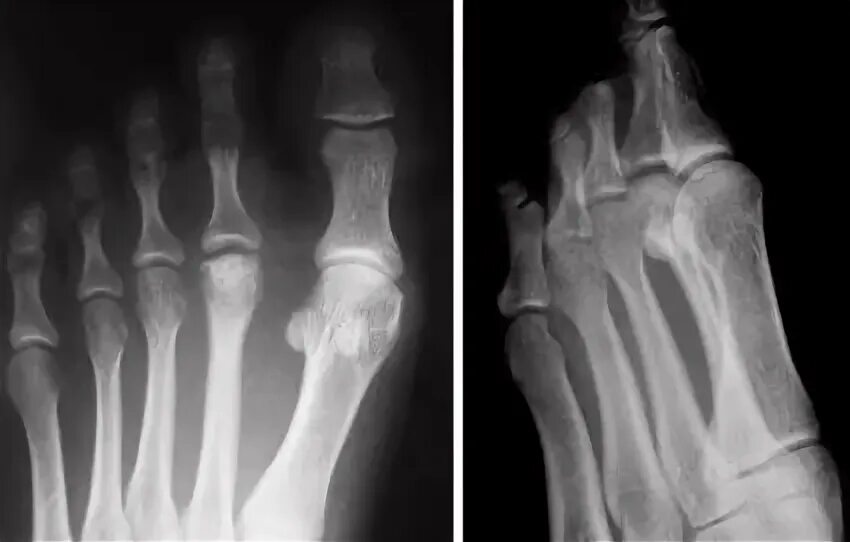

Келлера 3